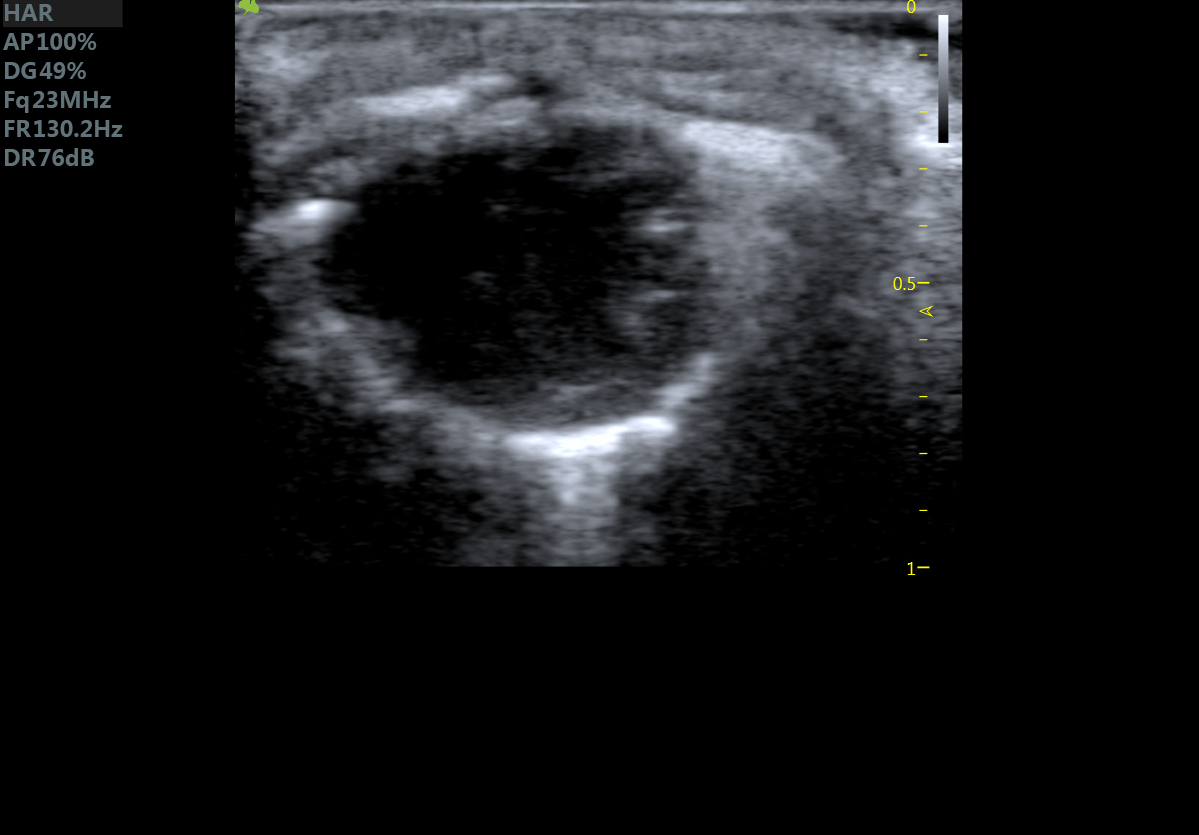

小鼠长轴M型 小鼠短轴M型

小鼠长轴B型 小鼠短轴B型

小鼠主动脉弓 小鼠肾脏血流

小鼠乳头肌水平 小鼠肝脏

大鼠短轴M型 大鼠长轴M型

大鼠长轴B型 大鼠主动脉弓

大鼠胎鼠心脏血流 大鼠心尖四腔

大鼠肝脏 大鼠肾脏